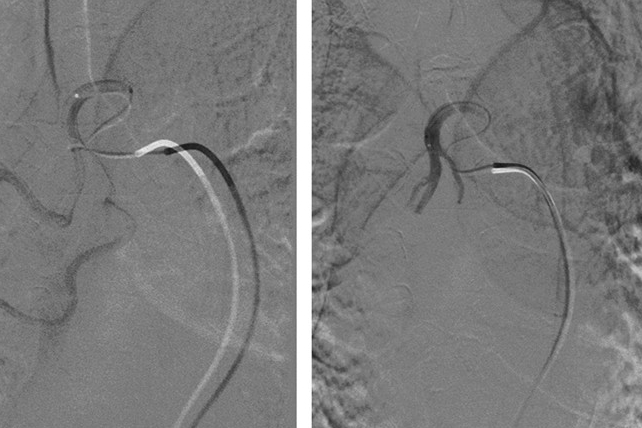

993术前突发大咯血 及时介入栓塞救性命

今年73岁的老王(化名),是我院呼吸内科的“老病号”了。这次他在术前突发大咯血,情况危急。幸而介入团队及时出动,在DSA下顺利止血,救了老王一命。反复咯血4年里住了9次院老王患上支气管扩张有30多年了。起初只是痰中带些血丝,近十年演变成了反复咯鲜血,咯血量逐年增多。今年2月中旬,老王再次因咯血住进了我院呼吸内科。这已经是四年里他第九次来我院住院治疗了。所幸在经过一段时间的药物保守治疗后,情况得到了...